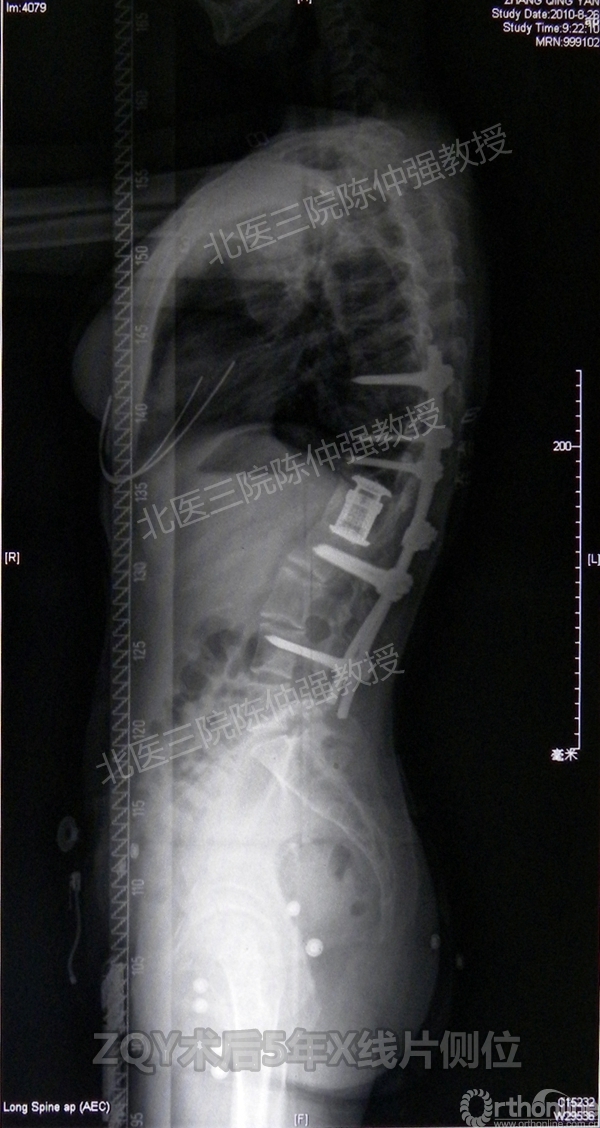

ZQY术后5年

患者女性17岁,胸腰椎陈旧结核性侧后凸畸形,局部呈“麻花状”扭转,无神经功能受损表现。2005年,陈仲强教授带领团队实施后路+侧前方联合入路脊柱节段切除、双轴旋转矫形术。术后患者外观显著改善,神经功能正常。术后随访证实患者截骨矫形节段骨性融合良好,矫形效果持续良好。